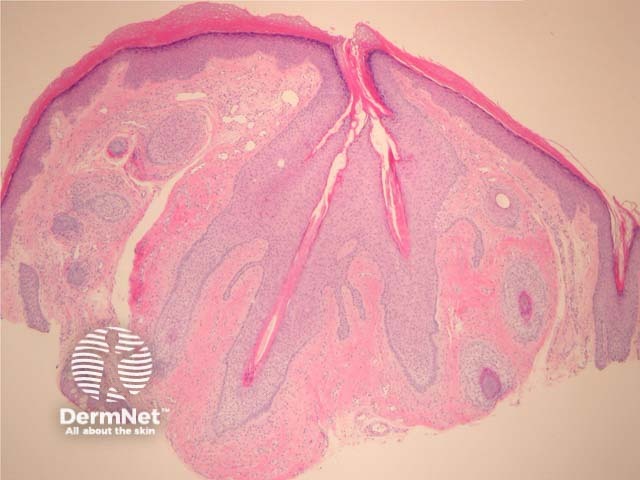

In trichofolliculoma, sections show numerous small follicles radiating from a central larger follicle. The hairs are surrounded by a well circumscribed dense stroma. (figures 1–3). The surrounding hairs are generally very small (vellus). Intermixed Merkel cells and sebocytes may be seen. A sebaceous variant has been described (sebaceous trichofolliculoma).

Figure 1